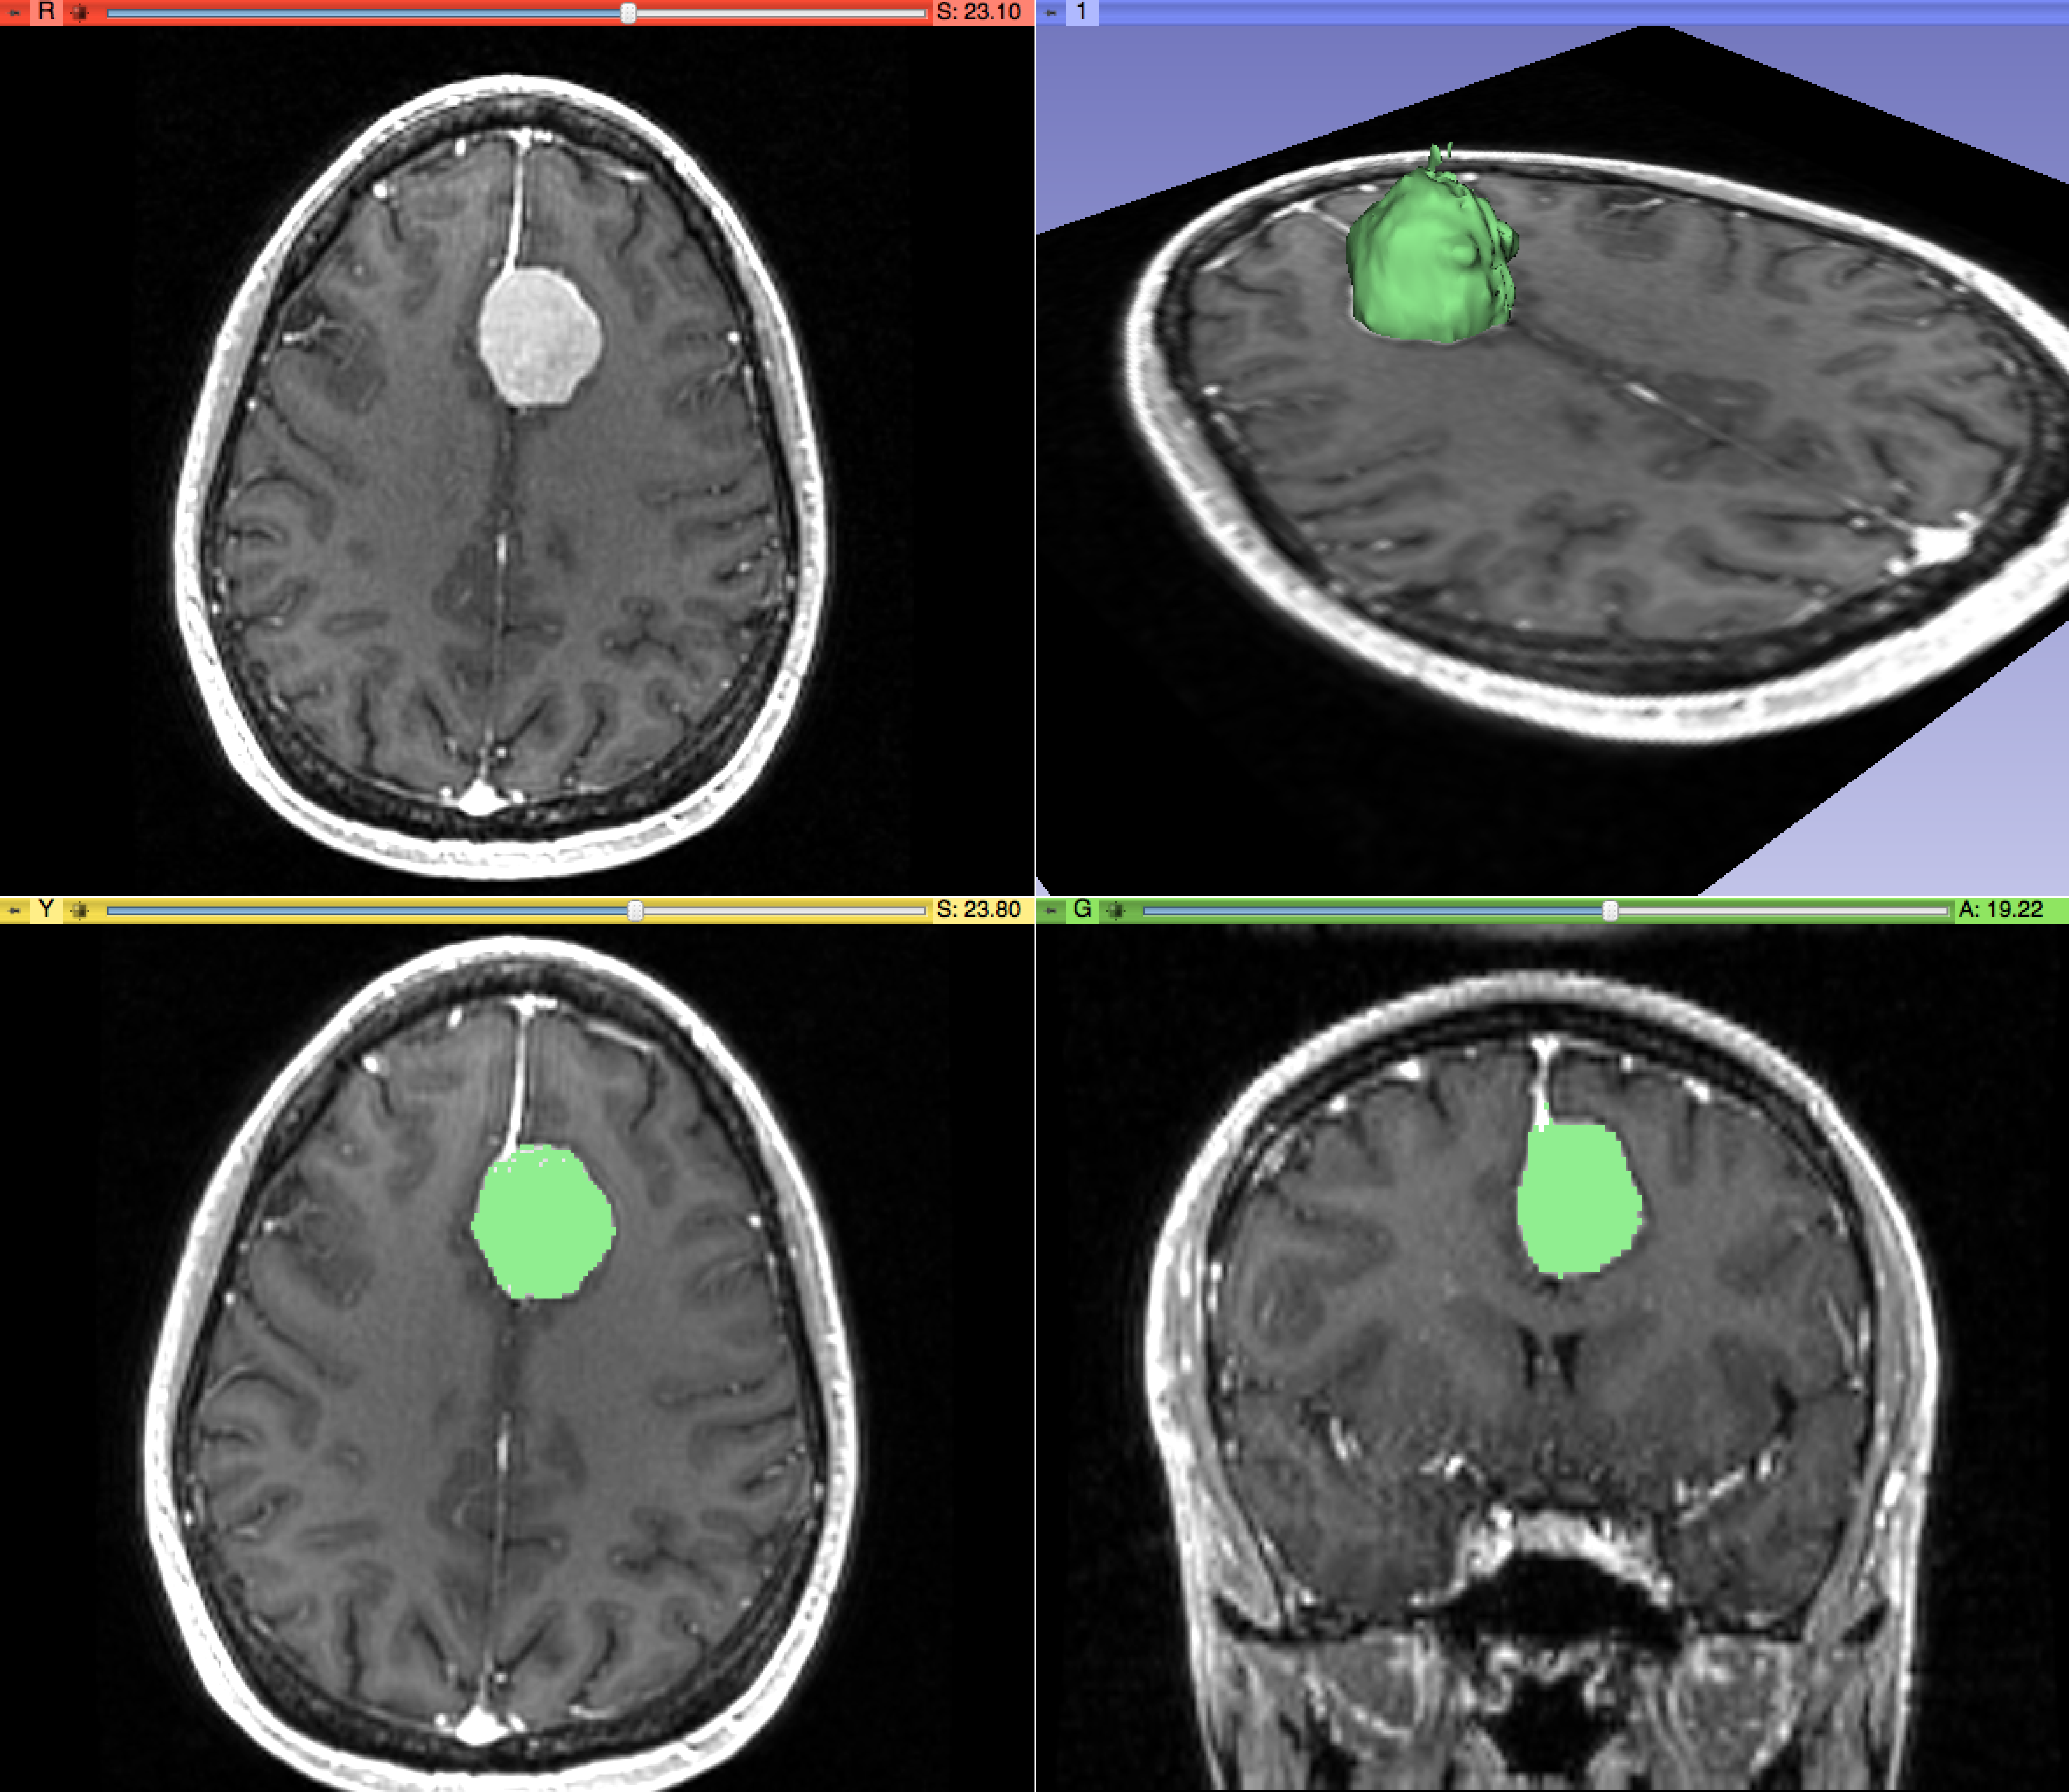

FFT 알고리즘, 이미지 처리, 음성 인식, 데이터 압축, 음성 합성은 데이터 처리의 주요 분야이다.[1] 정보는 이미지, 음향, 비디오 또는 기타 멀티미디어 형태를 취할 수 있으며, 정보의 비트는 신호를 통해 스트리밍될 수 있다.[1] 데이터 처리는 정보학의 중심 개념이며, 정보 처리 알고리즘을 연구한다.[1] 이 분야는 정보 이론, 통신, 정보 공학에서 중요한 역할을 하며, 의료 영상 컴퓨팅 및 음성 합성 등에 응용된다.[1]

의료 정보학 | ![]() |